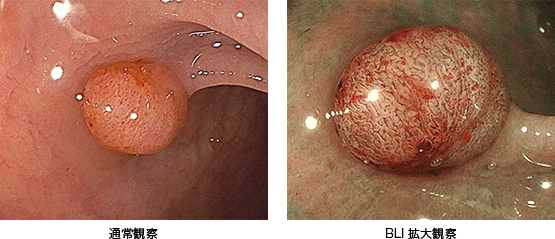

当院で採用している富士フイルム社製のレーザー内視鏡は、高精細なハイビジョン画像、画像強調機能(BLI)および最大135倍の光学拡大機能を持ち、微細な病変を詳細に観察することができます。また、腸管壁のカーブに沿ってスムーズにスコープが曲がる「カーブトラッキング技術」を搭載しており、苦痛の低減と検査時間の短縮を実現しています。

拡大内視鏡などで詳細な観察を行い、切除すべきかどうか判断します